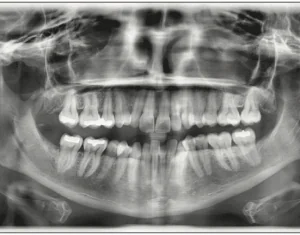

A Digital Approach to Aesthetic Restoration 2023-06-21 INTRODUCTION At age 14, I declared that I would be a dentist someday, but what I didn’t realize was how my work would allow me